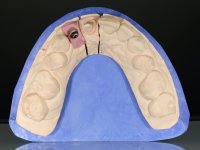

Primeira Fase.

O dente 1.1 foi preparado para uma coroa total, o afastamento gengival foi feito com caolino comprimido pela restauração provisória. A impressão foi feita com uma técnica de dupla mistura com dupla viscosidade. No laboratório foi confecionada uma coroa com infraestrutura em Zr revestida por cerâmica. A coroa foi cimentada em boca com cimento de ionómero de vidro reforçado por resina.